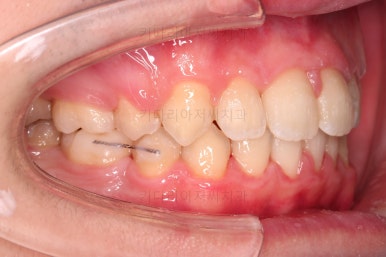

먼저 장치를 부착하고요.

환자분이 선택하신 장치는 자가결찰 메탈장치 입니다.

메탈이라고 모두 구시대적 장치는 아니에요. 자가결찰인지 아닌지가 구세대나 아니냐를 결정하는 기준이에요.

즉, 예를들면 자가결찰 메탈은 요즘세대, 그냥 세라믹은 구세대라 할 수 있어요.

자가결찰 중에서도 메탈도 있고 세라믹도 있는거고, 자가결찰 세라믹 중 클리피씨, 데이몬 클리어, 엠파워 클리어 등이 있습니다.

메탈은 강도가 높고, 부피도 작고, 위생관리에 약간의 장점이 더 있어요.

대신 보이는 측면에서의 단점이 있기 때문에 장단점을 고려해서 입맛에 맞게 선택하시라고 말씀 드리는 편이에요.

적절한 시기에 발치를 해주고요.

발치 공간을 이용해서 치열을 가지런하게 해줍니다.

가지런하게만 해도 발치공간이 거의다 없어져가요.